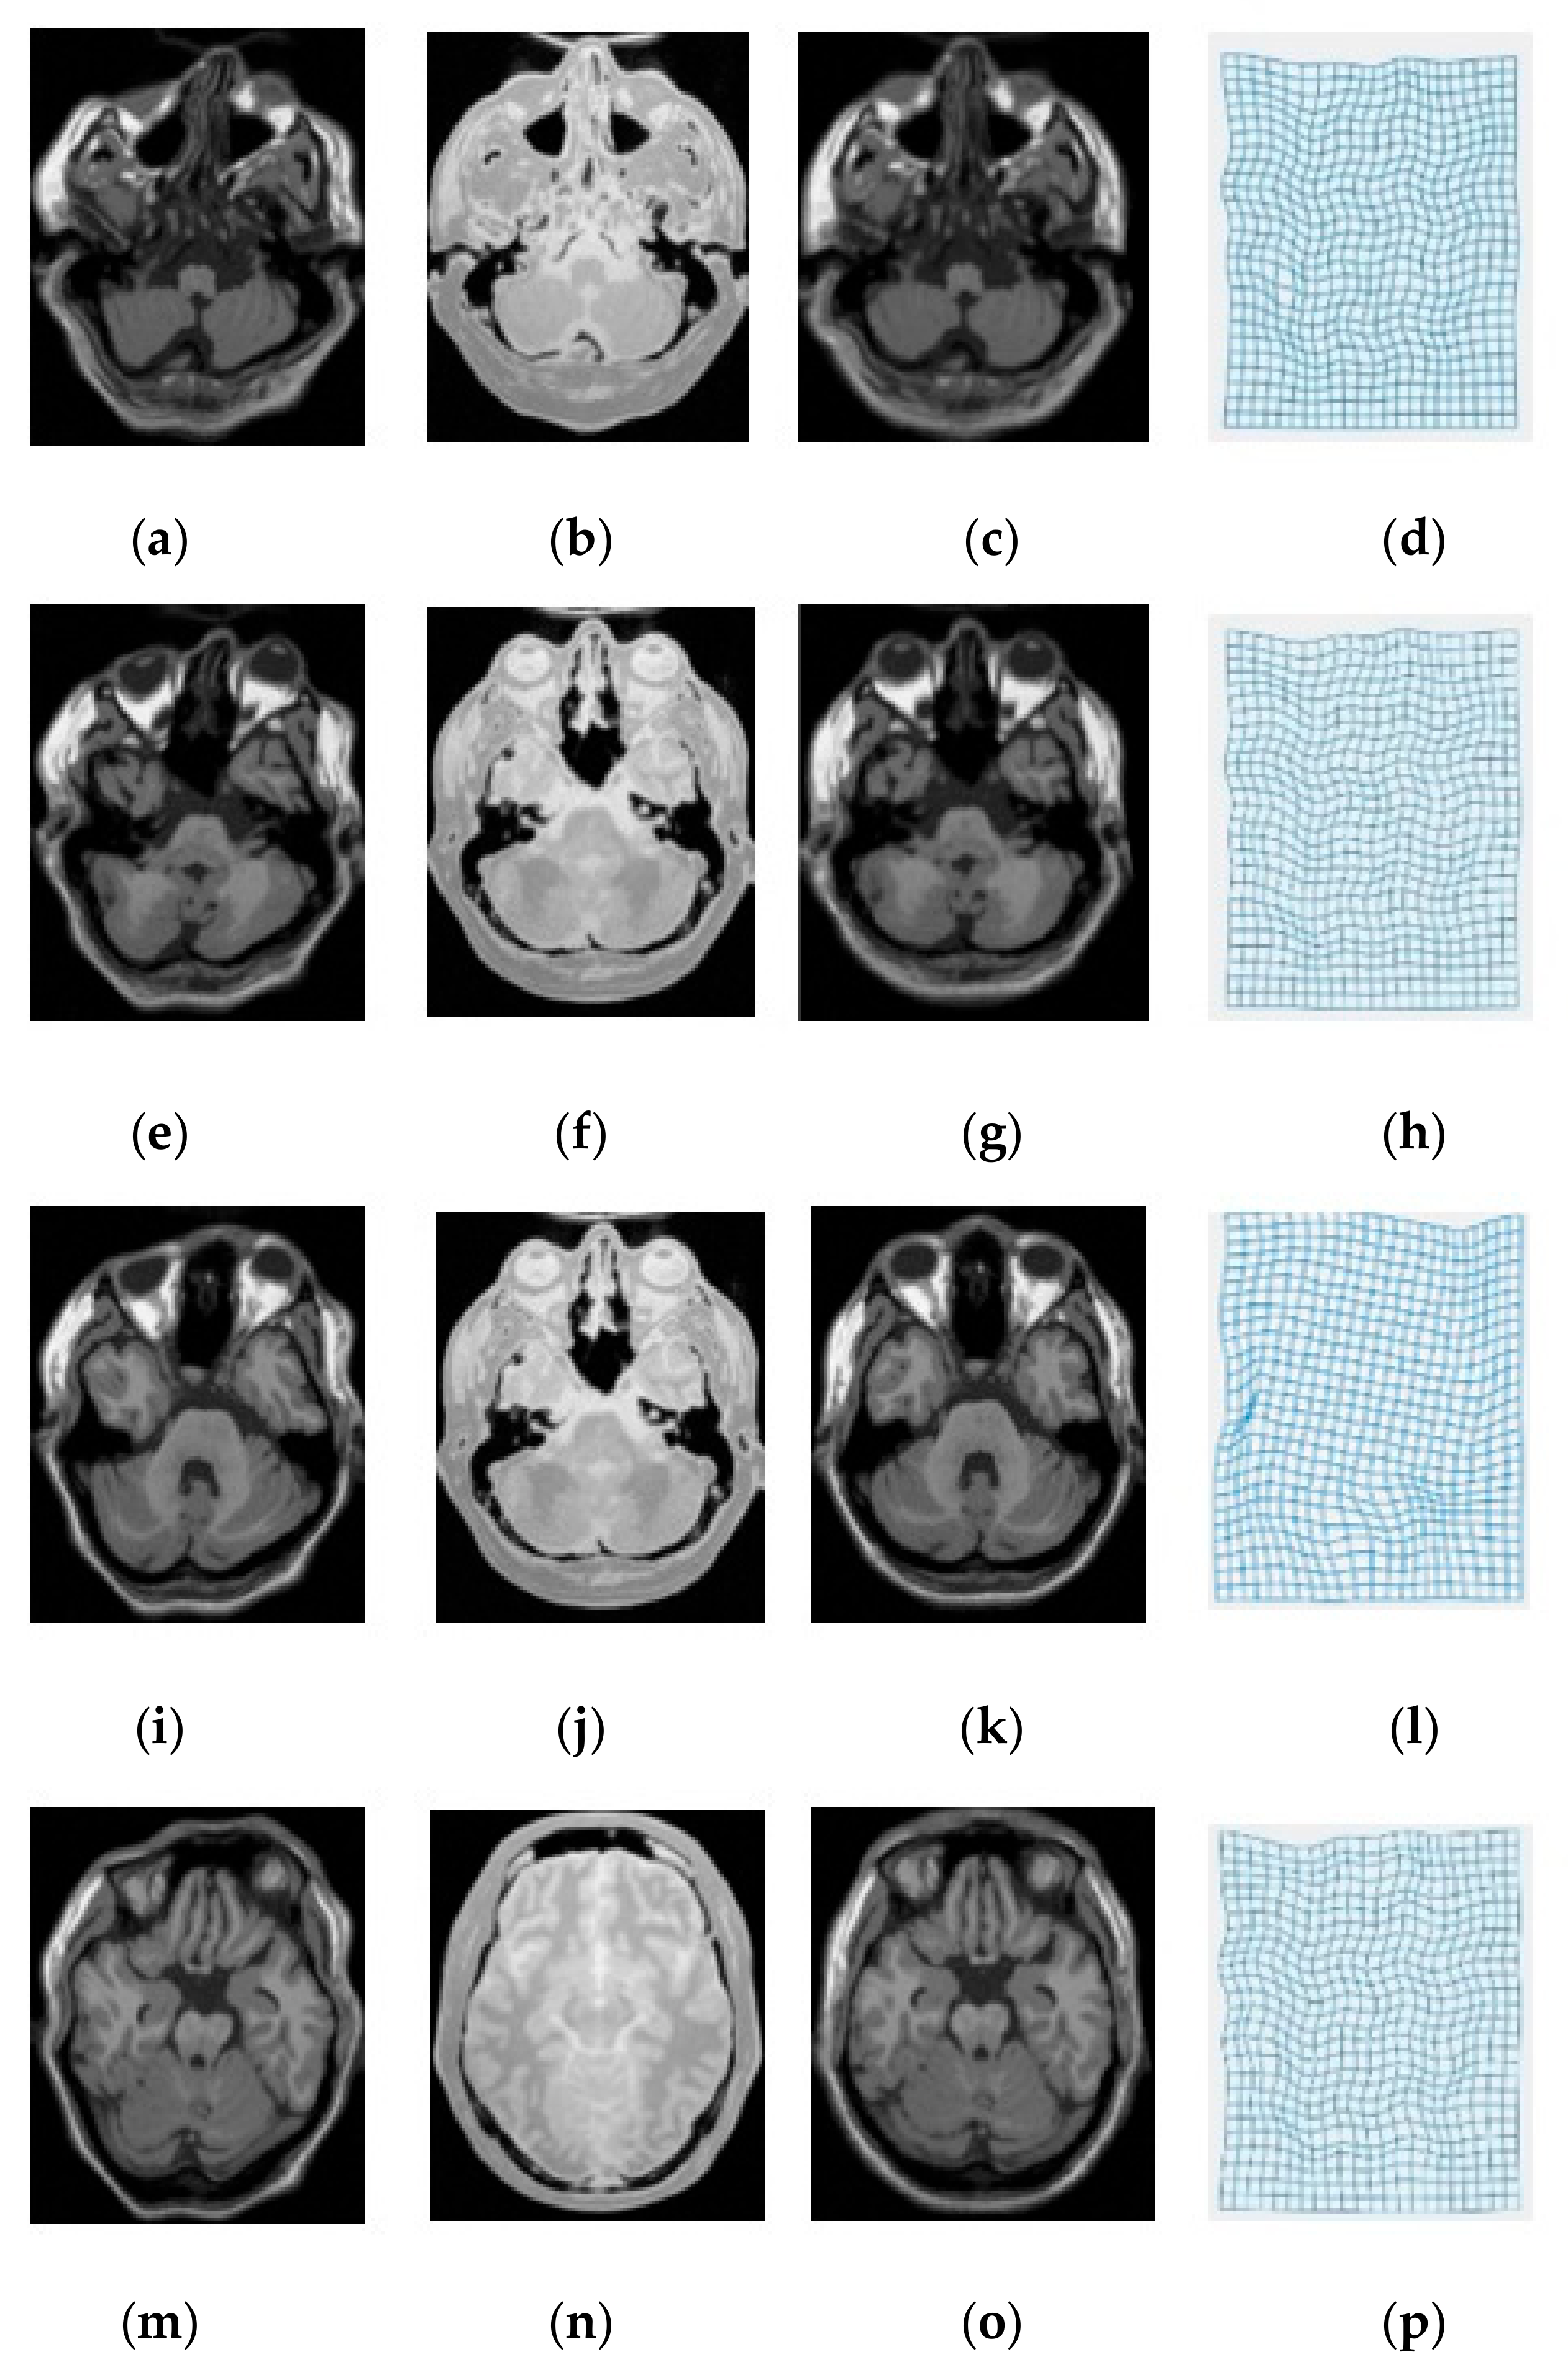

3. Experimental Results and Discussion

| Modality | MI [6] | SSC [21] | miLBP [25] | Ssesi [23] | miRID |

|---|---|---|---|---|---|

| T1-T2 | 2.63 | 2.35 | 2.42 | 2.45 | 2.04 |

| T1-PD | 2.88 | 2.16 | 2.26 | 2.42 | 2.13 |

| T2-PD | 3.01 | 2.47 | 2.36 | 2.47 | 2.01 |

| Average TRE | 2.84 | 2.33 | 2.35 | 2.45 | 2.03 |

| Average Time | 42.8 s | 39.6 s | 26.2 s | 35.4 s | 27.4 s |